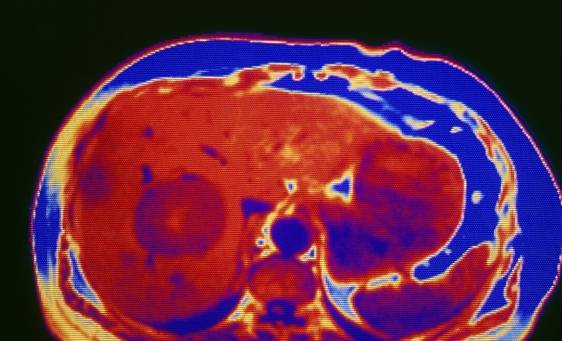

到医院做肝部CT或B超来查看肝脏状态 , 若检查发现肝脏体积缩小 , 表面不平整 , 边缘钝化 , 肝静脉变细 , 腹部有积液等症状 , 占一个 , 表明肝硬化就很严重了 。